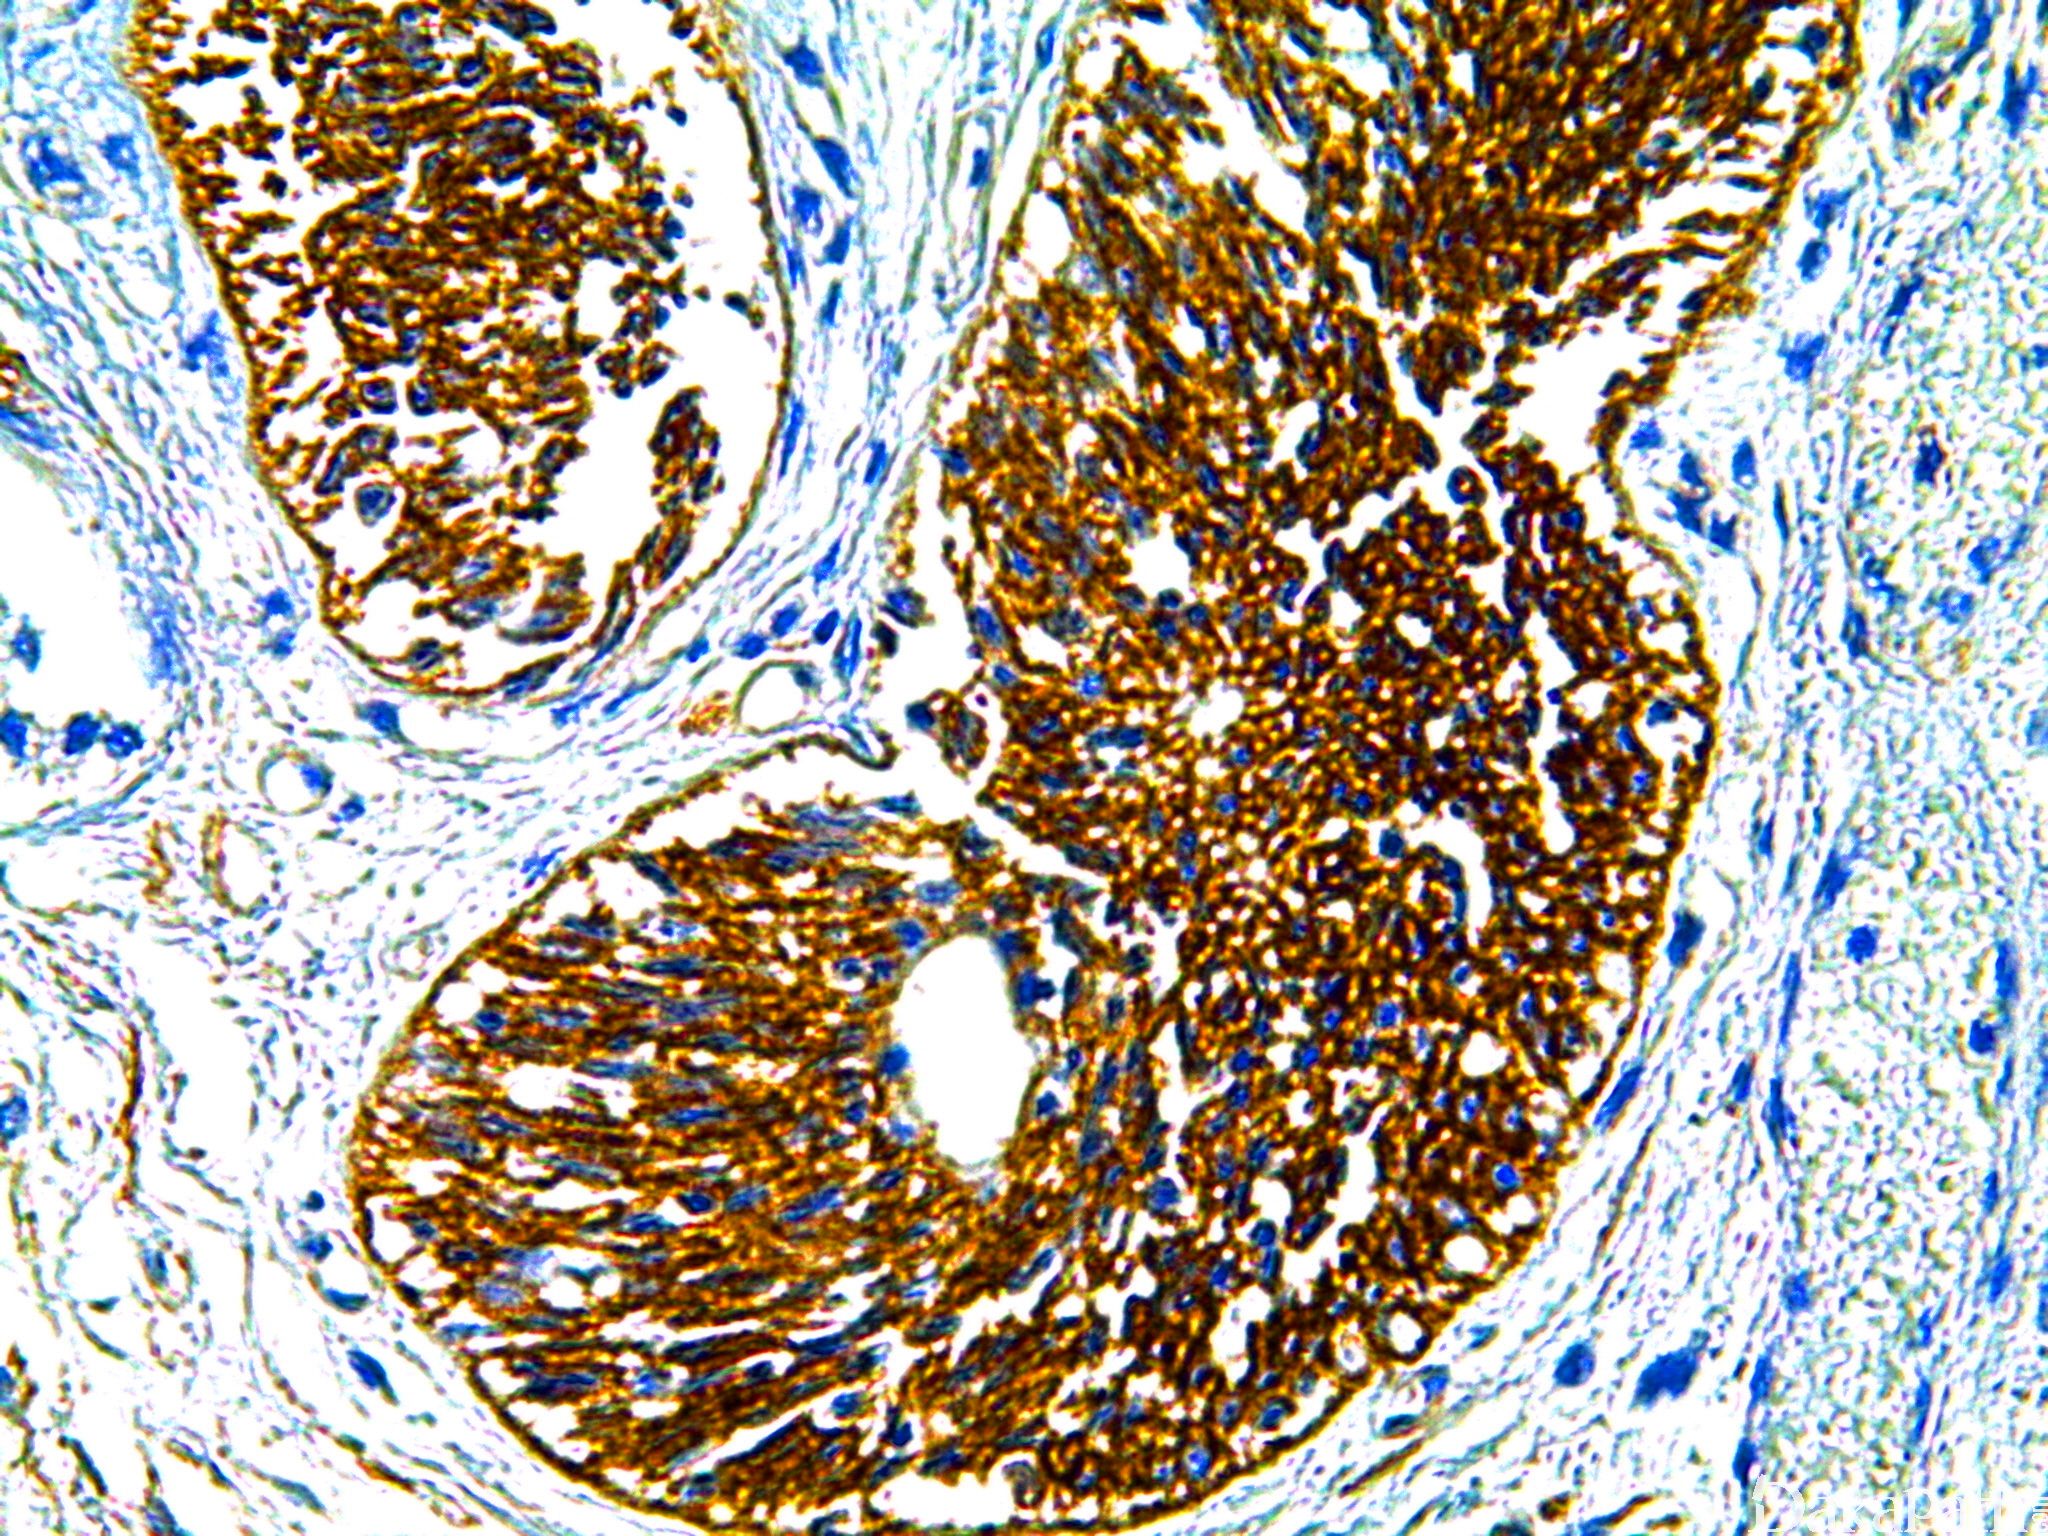

CD44

跨膜糖蛋白家族成员,介导细胞与细胞外基质的相互作用

信号定位: 胞膜

通常阳性(<95%,≥75%的病例阳性): 胃腺癌,弥漫性、毛黏液样星形细胞瘤、结直肠腺癌、上皮样间皮瘤、前列腺腺泡性癌、间皮瘤,NOS、宫颈鳞状细胞癌、膀胱尿路上皮癌、前列腺腺样囊腺癌,基底细胞、星形细胞瘤,高分化、阑尾囊腺瘤、膀胱腺癌,非特指型、间变性星形细胞瘤、套细胞淋巴瘤、乳腺导管内乳头状瘤